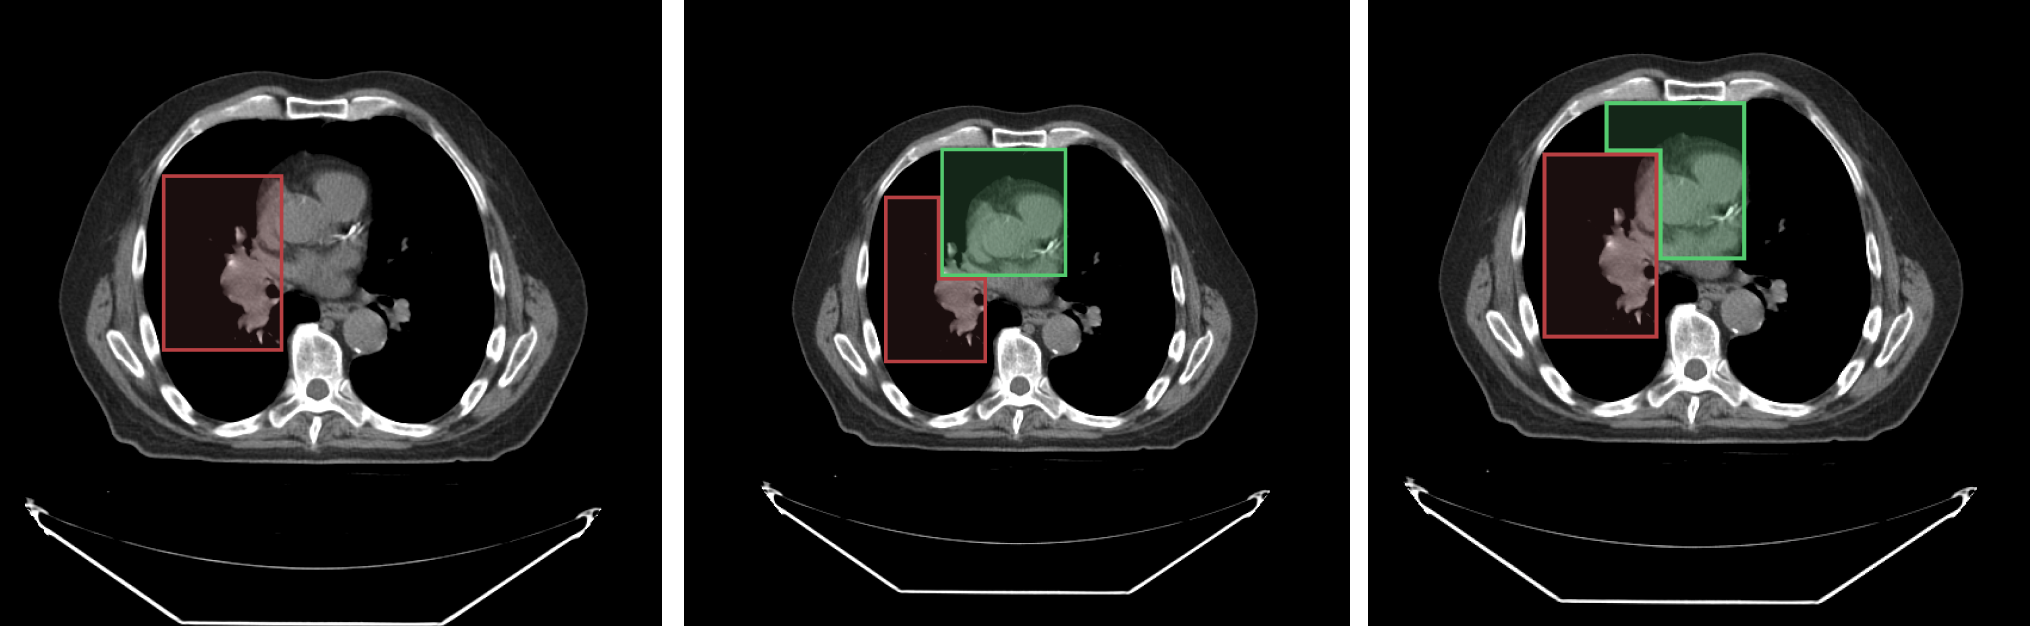

For example, consider the following image with an overlaid labelmap:

- Left image: shows

segment index 1 - Middle image: shows the result when

segment index 2is drawn on top ofsegment index 1 - Right image: shows the result when

segment index 1is locked andsegment index 2is drawn on top ofsegment index 1

As shown in the locked scenario (right image), when segment index 1 is locked, it cannot be modified by new drawings.